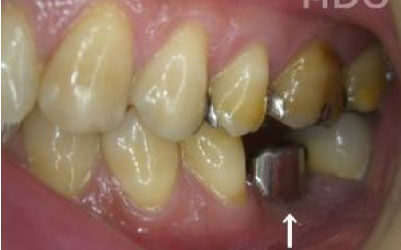

2 歯が傾いてくる、落ちてくる

歯はお互いに支え合ってバランスを取っています。ですので、歯が抜けるとその支えがなくなり、抜けた部分の隣の歯が倒れたり、上の歯が下に下がってくることがあります。